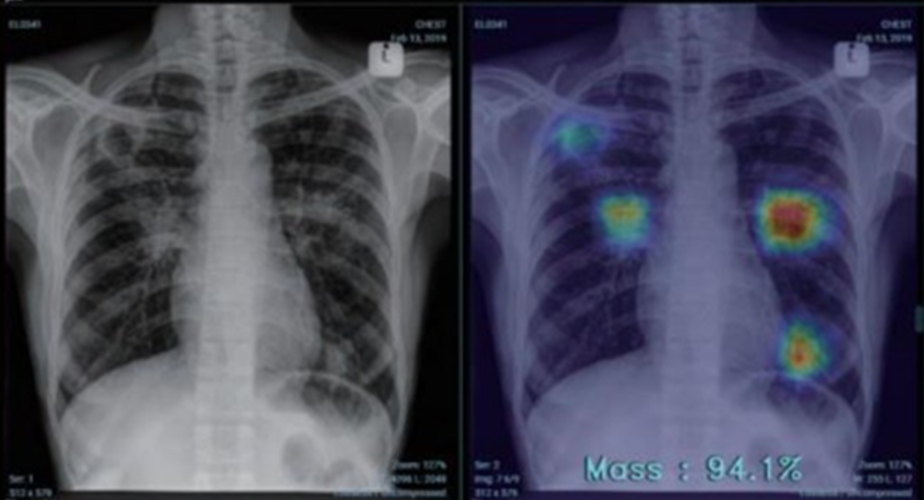

흉부 X-선 영상 AI 진단 보조

흉부 X선 영상 AI 진단보조는 AI(Artificial Intelligence, 인공지능)를 활용한 흉부 X선 영상 분석 솔루션입니다. 흉부 영상을 AI가 분석하여 결과를 시각화하고, 점수를 제공하여 의사가 보다 빠르고 정확하게 진단할 수 있도록 도와줍니다.

AI가 영상을 자동 인식해 정상과 비정상 부위를 시각적으로 표시하여 폐렴, 폐결핵, 폐암 등 16가지 폐 병변의 판독을 돕습니다. 이를 통해 다양한 폐질환의 조기 발견율을 높입니다.